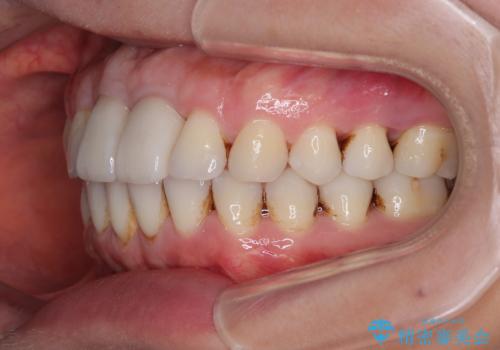

不適合なクラウンが装着されていたため、歯周ポケットが深くなっていましたので、矯正治療前に歯周外科処置を行って歯周ポケットを除去し、矯正治療後にオールセラミッククラウンにて補綴治療を行うこととしました。

前歯の見た目はもちろん、出血や腫脹のない健全な前歯の状態を獲得することができました。